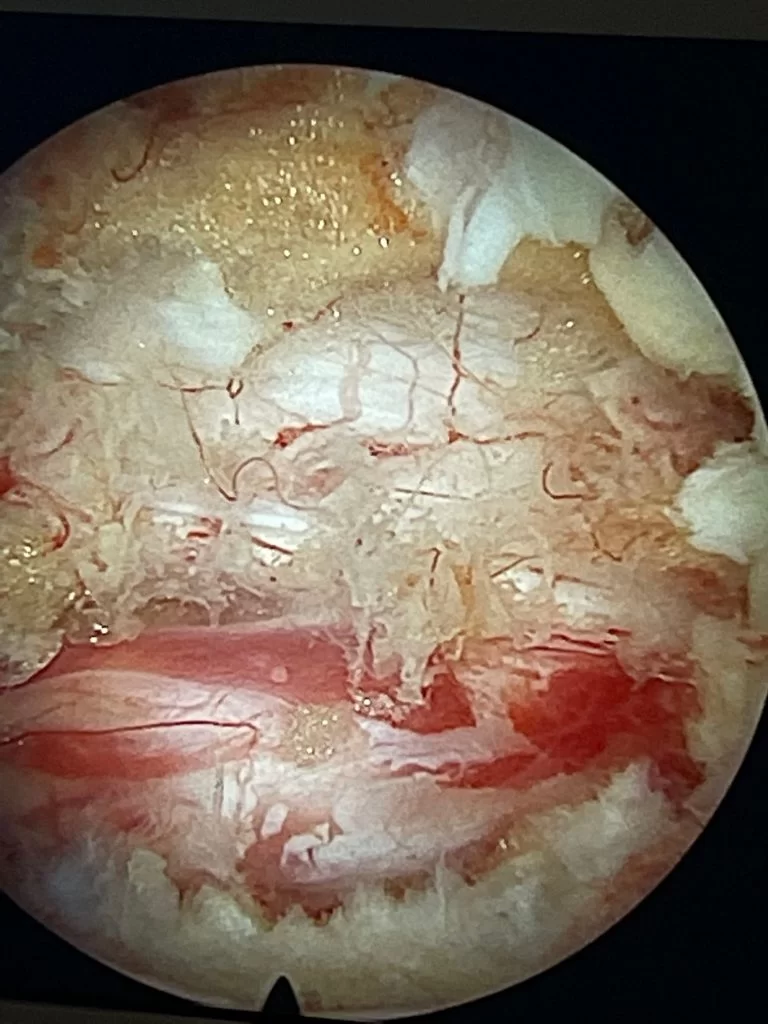

Θωρακικό Σβάννωμα Θ9/Θ10

Ασθενής γυναίκα 47 ετών με ραχιαλγία και άτυπα άλγη κάτω άκρων άμφω. Ο απεικονιστικός έλεγχος με μαγνητική τομογραφία ανέδειξε ευμεγέθη ενδο/εξωκαναλική χωροκατακτητική εξεργασία στο ύψος